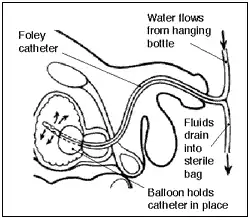

Las sondas de Foley son tubos flexibles, generalmente de látex, que en la cateterización urinaria se pasan a través de la uretra y hacia el interior de la vejiga. Este procedimiento se realiza por varios objetivos, uno de ellos es para obtener una muestra de orina libre de gérmenes, o bien para ayudar a aliviar una vejiga distendida.[1] Quedan retenidos por medio de un globo en la extremidad del catéter que se infla con agua estéril.[2] Los globos vienen típicamente en dos tamaños diferentes, 5 cm³ y 30 cm³.[3]

Los catéteres de tres vías se utilizan sobre todo después de las cirugías de la vejiga, la próstata, o el cáncer de próstata. Tienen un tercer brazo o campana que permiten que un irrigante pase por la extremidad del catéter a la vejiga a través de un pequeño canal separado. Esto sirve para limpiar sangre y pequeños coágulos a través de la rama principal que drena en un dispositivo de recolección.[6]